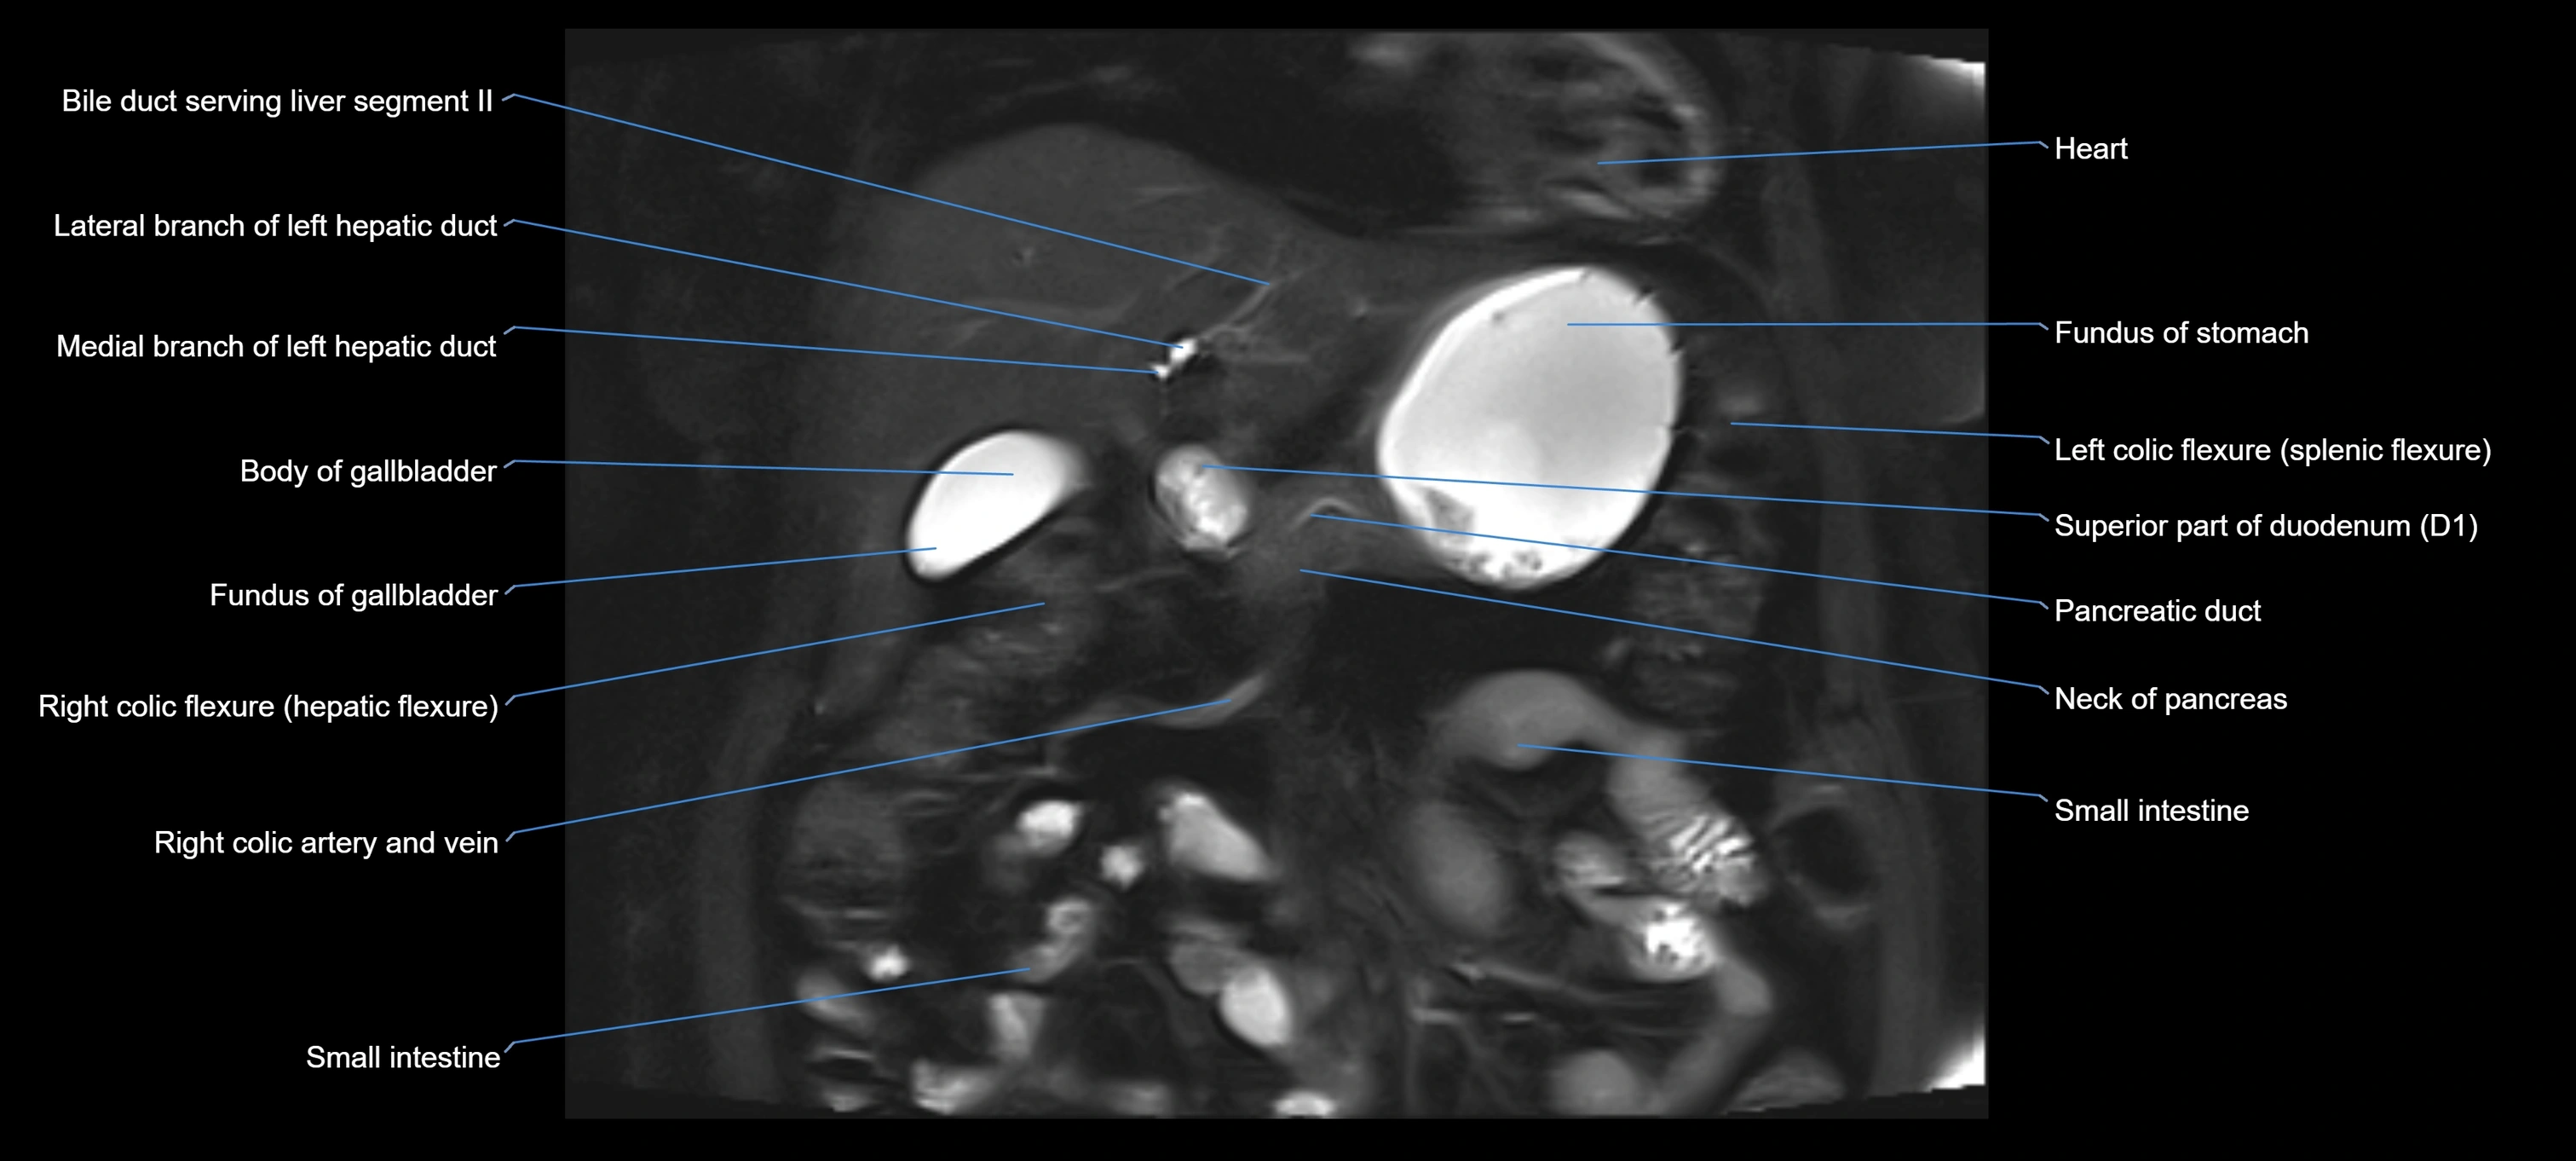

MRI image

image

Fullscreen Image